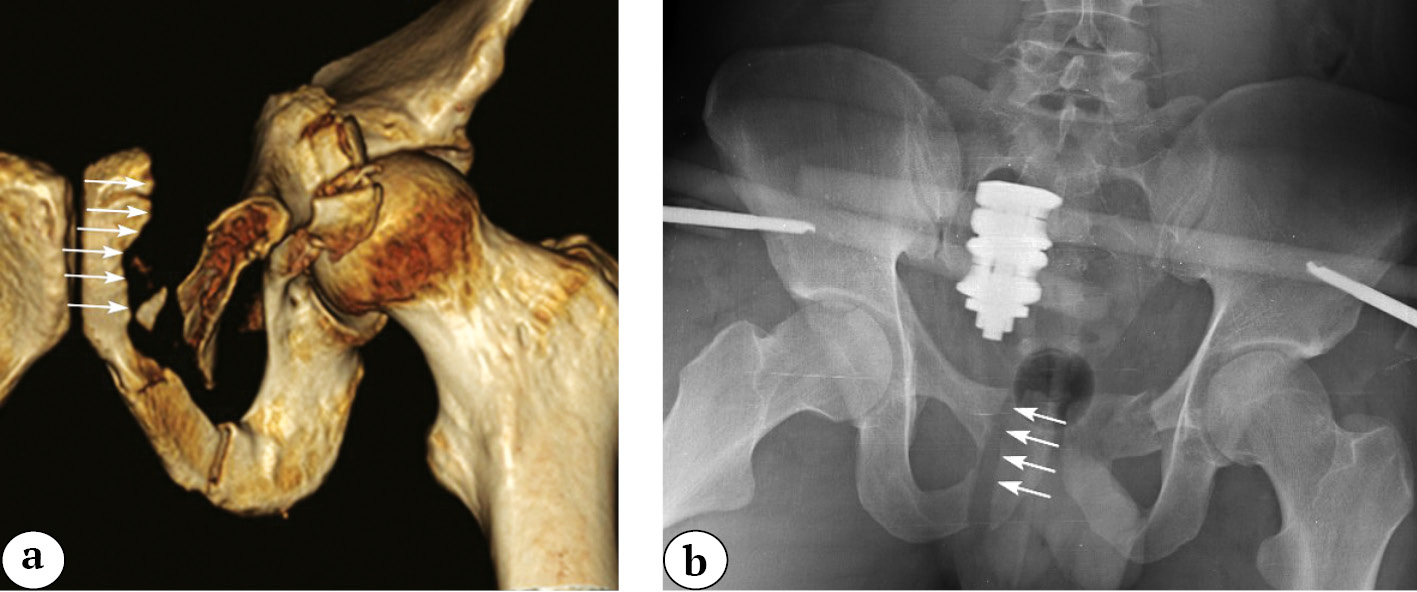

In the practice of traumatologists, there are some cases of transrectal fractures of the acetabulum with the extension of the fracture line into the calcar region, forming a characteristic sharp end called a “calcar spike.”

The morphology of such a fracture is determined by the orientation of the bone trabeculae in this area (see Figure 12). A similar phenomenon can be observed in nature — wood always splits along its fibers. Similarly, in the case of pelvic fractures, the fracture line extends from the acetabulum to the calcar, splitting it along the bone trabeculae, resulting in the formation of a sharp end (calcar spike) (Fig. 13).

The calcar spike is an important diagnostic sign. It is a pathognomonic feature of high (transtectal or juxtatectal) fractures of the posterior column or transtectal fractures of the acetabulum, which require surgical treatment to restore joint congruence.

The clinical interest in this situation primarily arises from the intimate proximity of the relatively large superior gluteal artery and the sciatic nerve to the sharp end of the posterior column fracture (Fig. 14a). The artery and nerve can be damaged both directly during the trauma and iatrogenically when attempting to expose them during open reduction of the fracture. Intraoperative bleeding from the superior gluteal artery can pose an existential threat to the patient and requires careful preoperative preparation. Damage to the sciatic nerve can lead to neurological deficits, potentially resulting in impaired lower limb support function and significant pain syndrome.

In our opinion, when a calcar spike is present, it is advisable to perform a pelvic CT scan with contrast to visualize the vessels of the internal iliac artery and rule out damage to the superior gluteal artery. If the artery is already damaged or is at a safe distance from the spike’s tip, open reduction can be performed using the conventional technique.

In cases where the calcar spike is in close proximity to the preserved superior gluteal artery, we recommend performing an osteotomy of a sharp end of spike that is in contact with the vessel (Fig. 14b). This approach significantly reduces the risk of damaging the artery during its dissection and repositioning maneuvers with the remaining fragment of the posterior column.

Fig. 14. Superior gluteal artery (a); osteotomy of the calcar spike, the arrow marks the level of osteotomy (b)

For surgeons with sufficient experience and specialized instruments, it is possible to carefully dissect the calcar spike from soft tissues and perform open reduction using the “palisade technique” with the use of J. Matta’s forceps [17]. Thanks to the high bone density in the calcar region, the fragment does not split even under substantial repositioning forces (Fig. 15).

Fig. 15. Open reduction of the calcar spike with Matta clamp and plate fixation